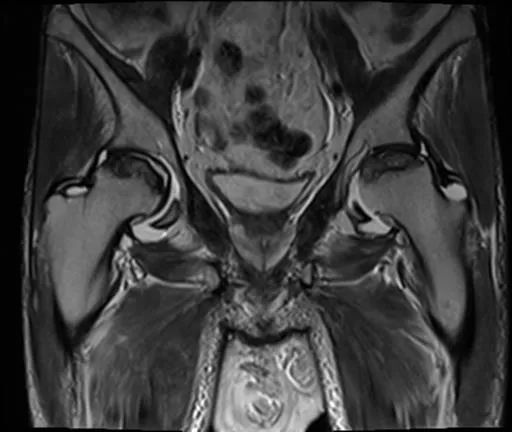

双侧股骨头前上面有大面积的骨髓异常,T1为低信号,在T1和T2W图像上,周围环绕着低强度的边缘。双股骨头呈线性软骨下骨折/断裂,在脂肪抑制图像上得到很好的评价。两侧均有轻度塌陷/扁平的轻微轮廓畸形。这些发现代表了双侧股骨头缺血性坏死。

骶髂关节和耻骨联合正常。

盆腔内存在小体积游离液。弥漫性软组织水肿见于前腹壁及骨盆、大腿。这些发现是由于慢性肾脏疾病造成的。

这是典型的双边缺血性坏死有特征性的X线和MRI表现。患者有SLE合并狼疮性肾炎并接受类固醇治疗,均易发生AVN。